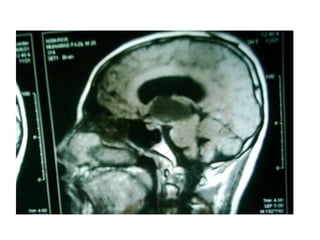

Investigation U ltrasonography to visualize the ventricular system(when the anterior fontanelle is patent). Also for antenatal diagnosis CT and /or MRI of the head; it is important to exclude any abnormal masses and to study the size and the shape of the ventricles, and some time needs contrast study.  LP in cases of communicating hydrocephalus for both diagnostic and therapeutic…..( NPH)

Investigation U ltrasonographyto visualize the ventricular system(when the anterior fontanelle is patent). Also for antenatal diagnosis CT and /or MRI of the head; it is important to exclude any abnormal masses and to study the size and the shape of the ventricles, and some time needs contrast study. LP in cases of communicating hydrocephalus for both diagnostic and therapeutic…..( NPH)